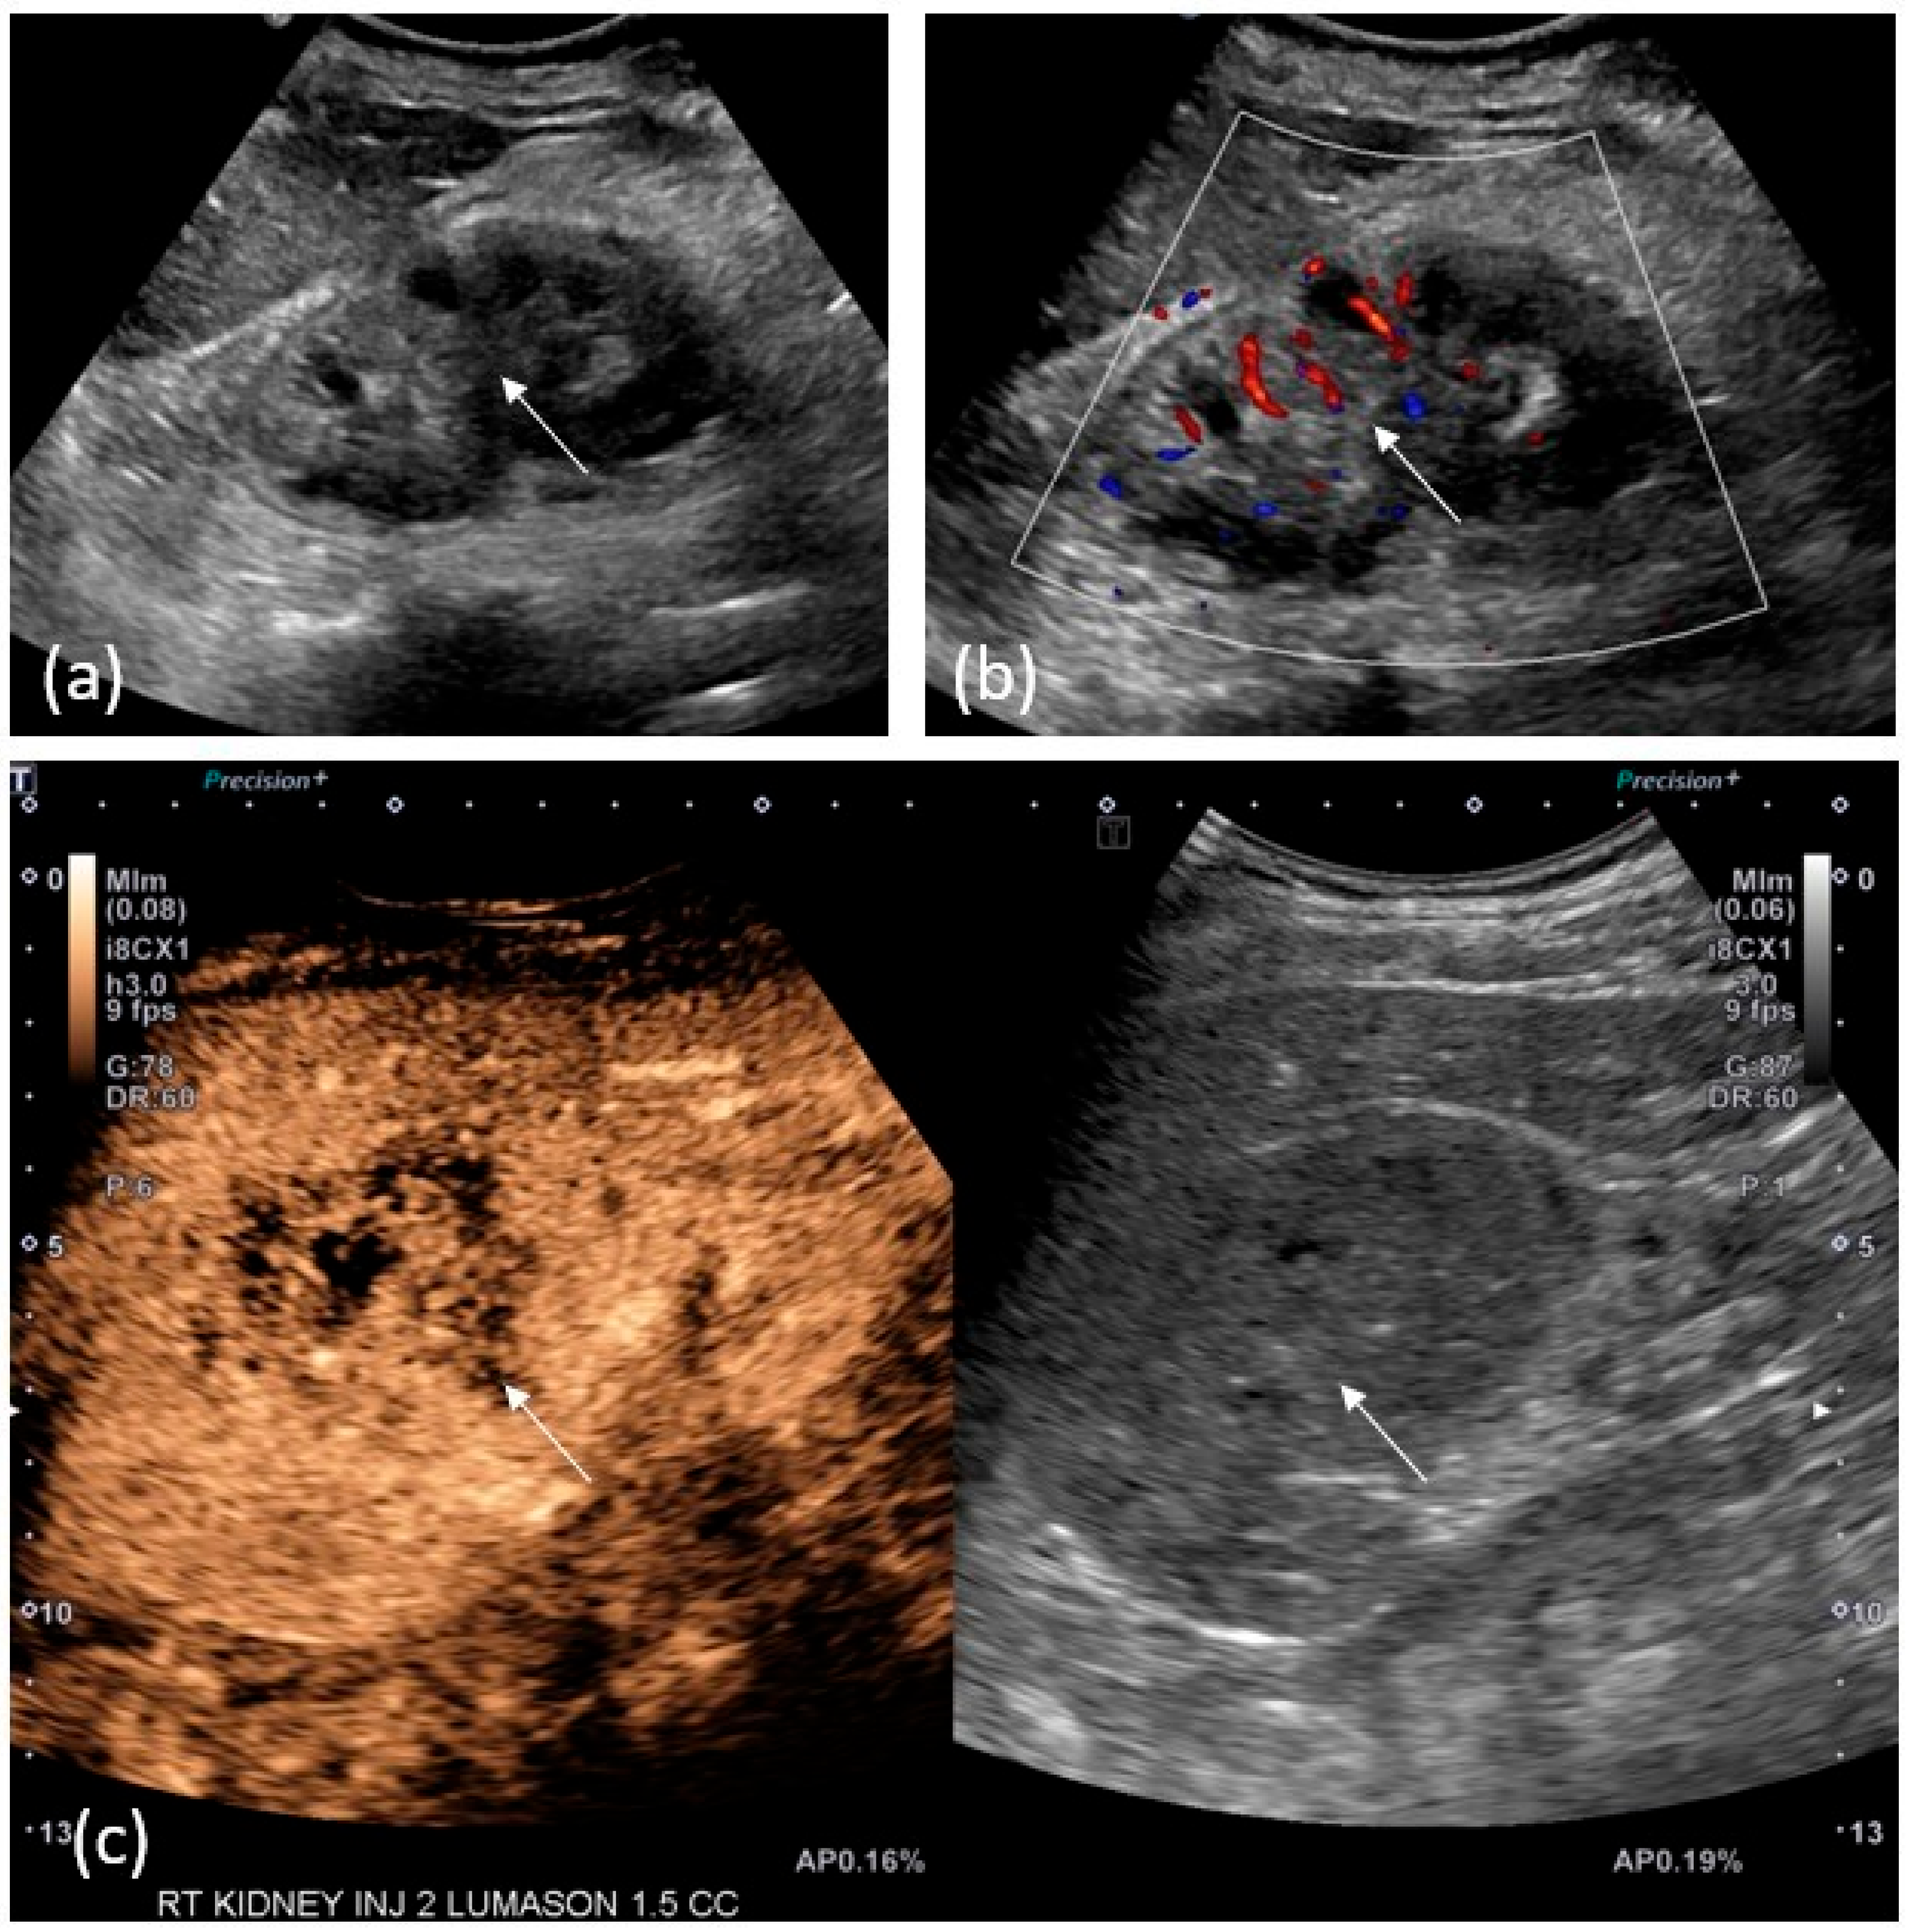

2.4. US/CEUS

- Seguel, A.P.; Pérez, M.M.; González, T.R.; Gómez, D.; del Río, J.V.; Benítez, G.M. Evaluation of upper tract urothelial carcinomas by contrast-enhanced ultrasound. Radiol. (Eng. Ed.) 2018, 60, 496–503. [Google Scholar] [CrossRef]

- Xue, L.-Y.; Lu, Q.; Huang, B.-J.; Li, C.-L.; Yan, C.-J.; Wen, J.-X.; Wang, W.-P. Evaluation of renal urothelial carcinoma by contrast-enhanced ultrasonography. Eur. J. Radiol. 2013, 82, e151–e157. [Google Scholar] [CrossRef]

- Drudi, F.M.; Di Candio, G.; Di Leo, N.; Malpassini, F.; Gnecchi, M.; Cantisani, V.; Iori, F.; Liberatore, M. Contrast-enhanced ultrasonography in the diagnosis of upper urinary tract urothelial cell carcinoma: A preliminary study. Ultraschall Med.—Eur. J. Ultrasound 2012, 34, 30–37. [Google Scholar] [CrossRef]